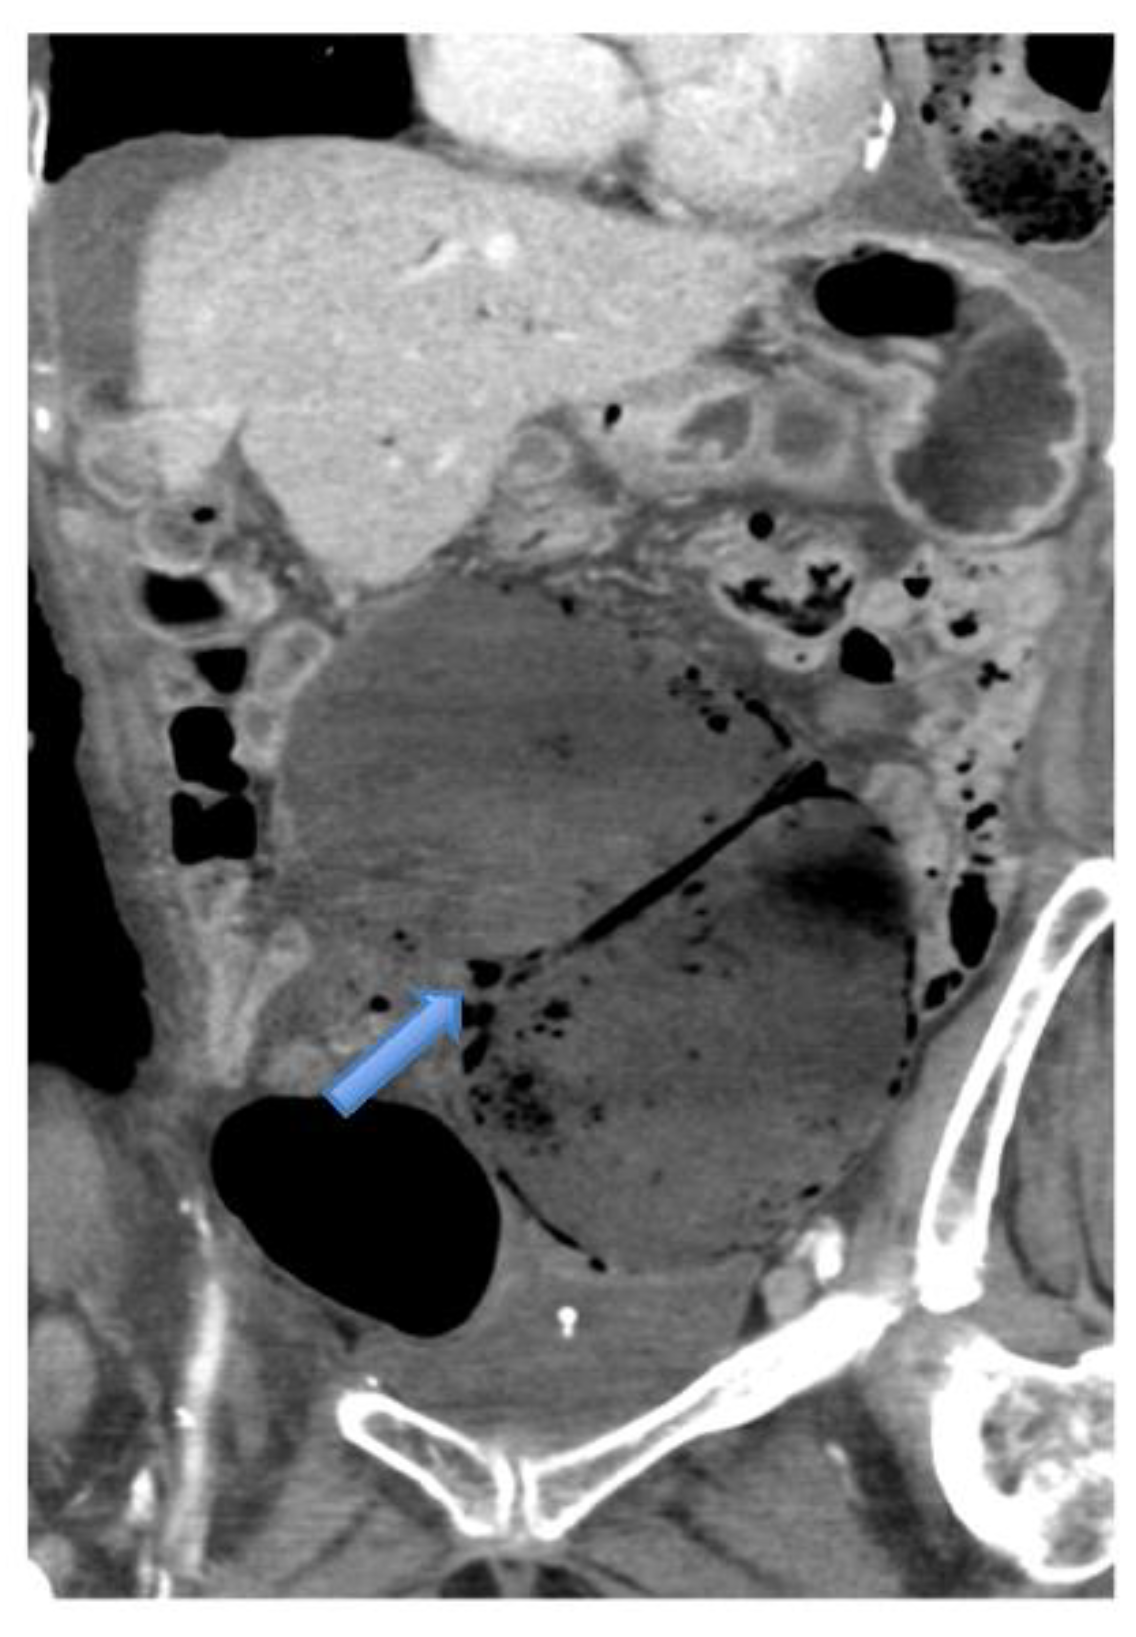

4.4.2. Computerised Tomography (CT) Scan

| CT Abdomen and pelvis | 15 | One patient operated without CT. |

| CV not described | 1 | |

| CV correctly identified | 14 (93.3%) | |

| Caecal diameter >10 cm | 10 (67%) | |

| Whirl sign | 12 (80%) | |

| Split-wall sign | 13 (86.6%) | |

| X-marks-the-spot sign | 14 (93.3%) | |

| Double transition point | 13 (86.6%) | |

| Ileocaecal twist | 13 (86.6%) | |

| Central appendix | 11 (73.3%) |